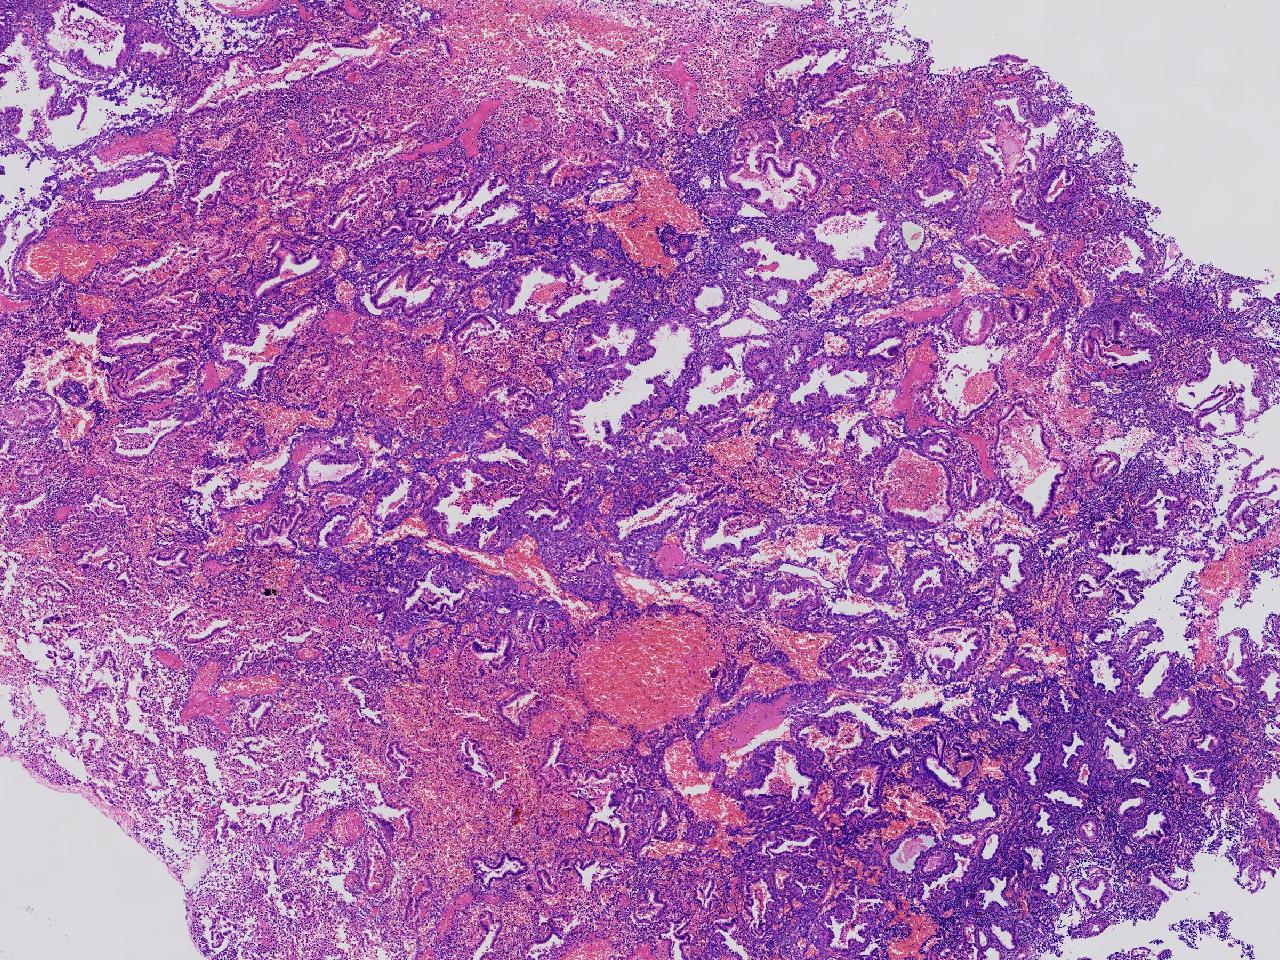

性别

女

年龄

45岁

临床诊断

阴道不规则出血20余天,

一般病史

彩超示:宫腔内见约41X11毫米的不均质回声区。宫腔镜示:宫腔形态正常,内膜粉红,不规则增厚。

标本名称

子宫内膜

大体所见

灰粉色不整形软组织多块,1.5X1X0.6厘米。

分泌反应子宫内膜,伴有出血。

晚泌期及月经早期改变,局部呈啫酸性乳头状化生改变。